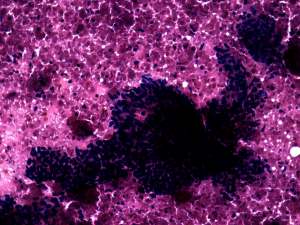

Cytology resulted in papillary cancer.

• The less obvious failure was my cytological diagnosis. Knowing the final diagnosis, of course, I would say otherwise. And re-examining the cytology sample later helped to avoid a similar mistake. Although the cytological picture resembles that seen in papillary cancer, the cytological pattern should raise colonic cancer. The clue is the palisading arrangement of tumor cells.